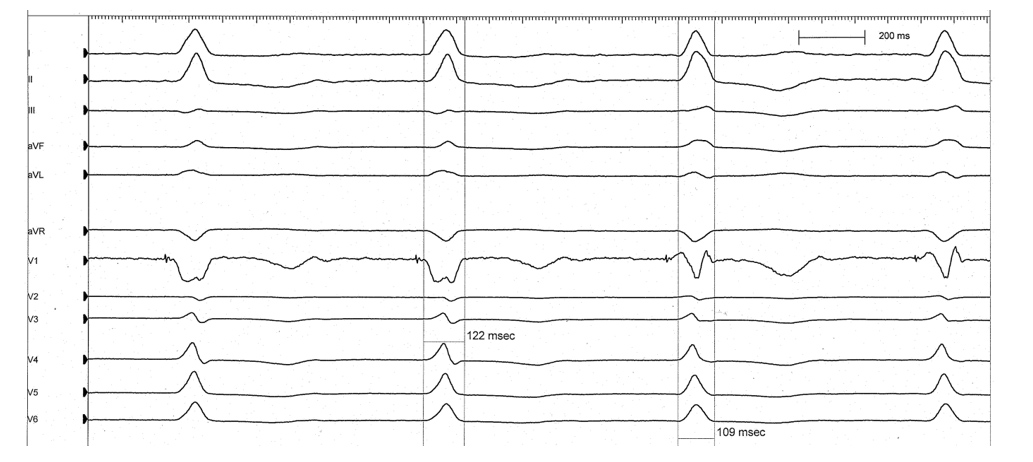

A ventricular threshold test was performed and it was noted that the morphology of the paced QRS complex changed during the test prior to a loss of ventricular capture. The test was conducted in VVI mode, decrementing from an output of 5.0 V. The change in QRS morphology occurred at an output of 2.5 V remaining this way until capture was lost at 0.5 V. The QRS duration also changed from 122 ms to 109 ms at this time.

Figure 1. ECG of the ventricular threshold test with the paced QRS morphology change highlighted.